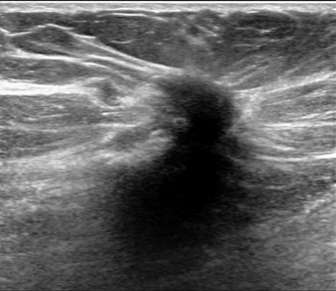

Hypoechoic mass with indistinct margins

The above ultrasound demonstrates a hypoechoic (dark) mass with indistinct margins, posterior shadowing, and distortion of the normal breast tissue. This was biopsied, revealing invasive ductal carcinoma (IDC). Both ductal carcinoma in situ (DCIS) and IDC may result in distortion.